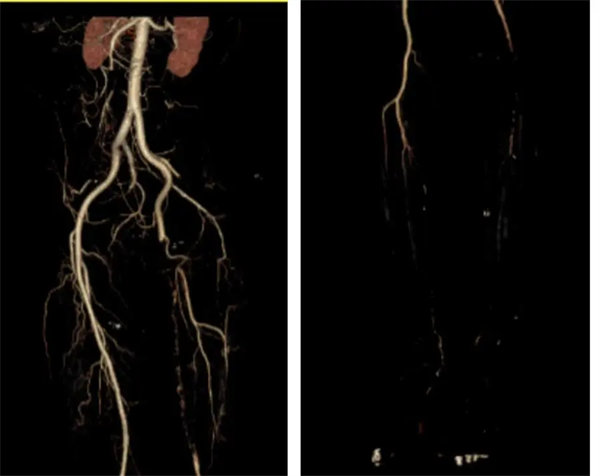

4月1日張師傅因左下肢發涼、疼痛,難以耐受,遂再次來院。入院時左下肢皮溫低,雙側股動脈可觸及,左側腘動脈、足背動脈未觸及。柏杖勇副主任醫師認真評估病情,在馮建新主任的指導安排下,完善術前檢查----下肢動脈CTA,提示左側髂外動脈下段閉塞。

CTA:左側髂外動脈閉塞